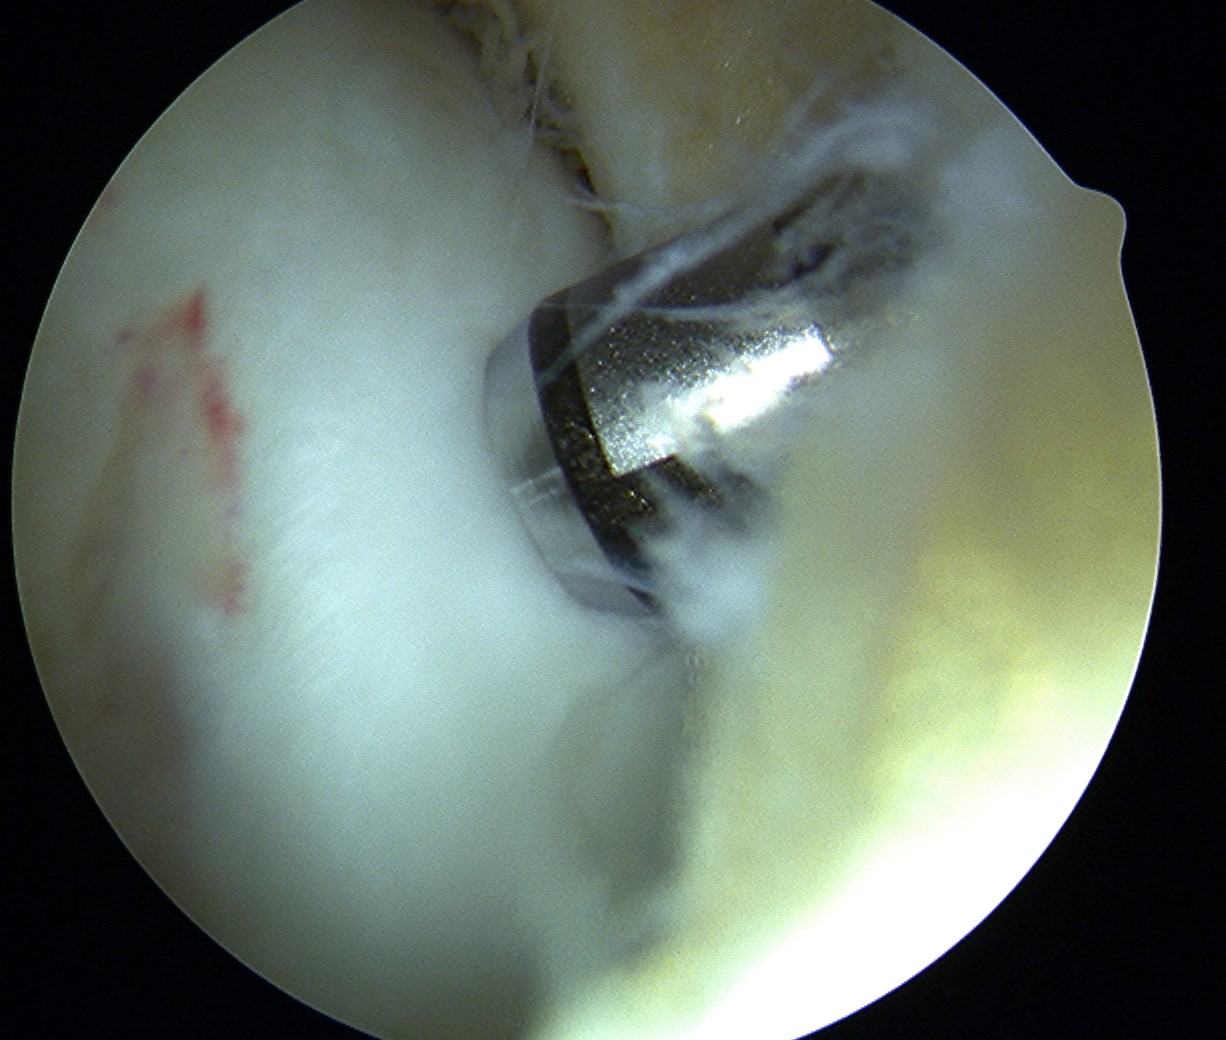

Drill site of mosaicplasty with 4.5 mm drill

- overdrill 2 - 4 mm

- do not want to leave plug proud

- impossible to sink further or remove

Insert dilator

Insertion device

- place over drill hole

- impact with hammer to seat in cartilage

- insert plug

- use tap to insert plug

- best to countersink 1 - 2 mm